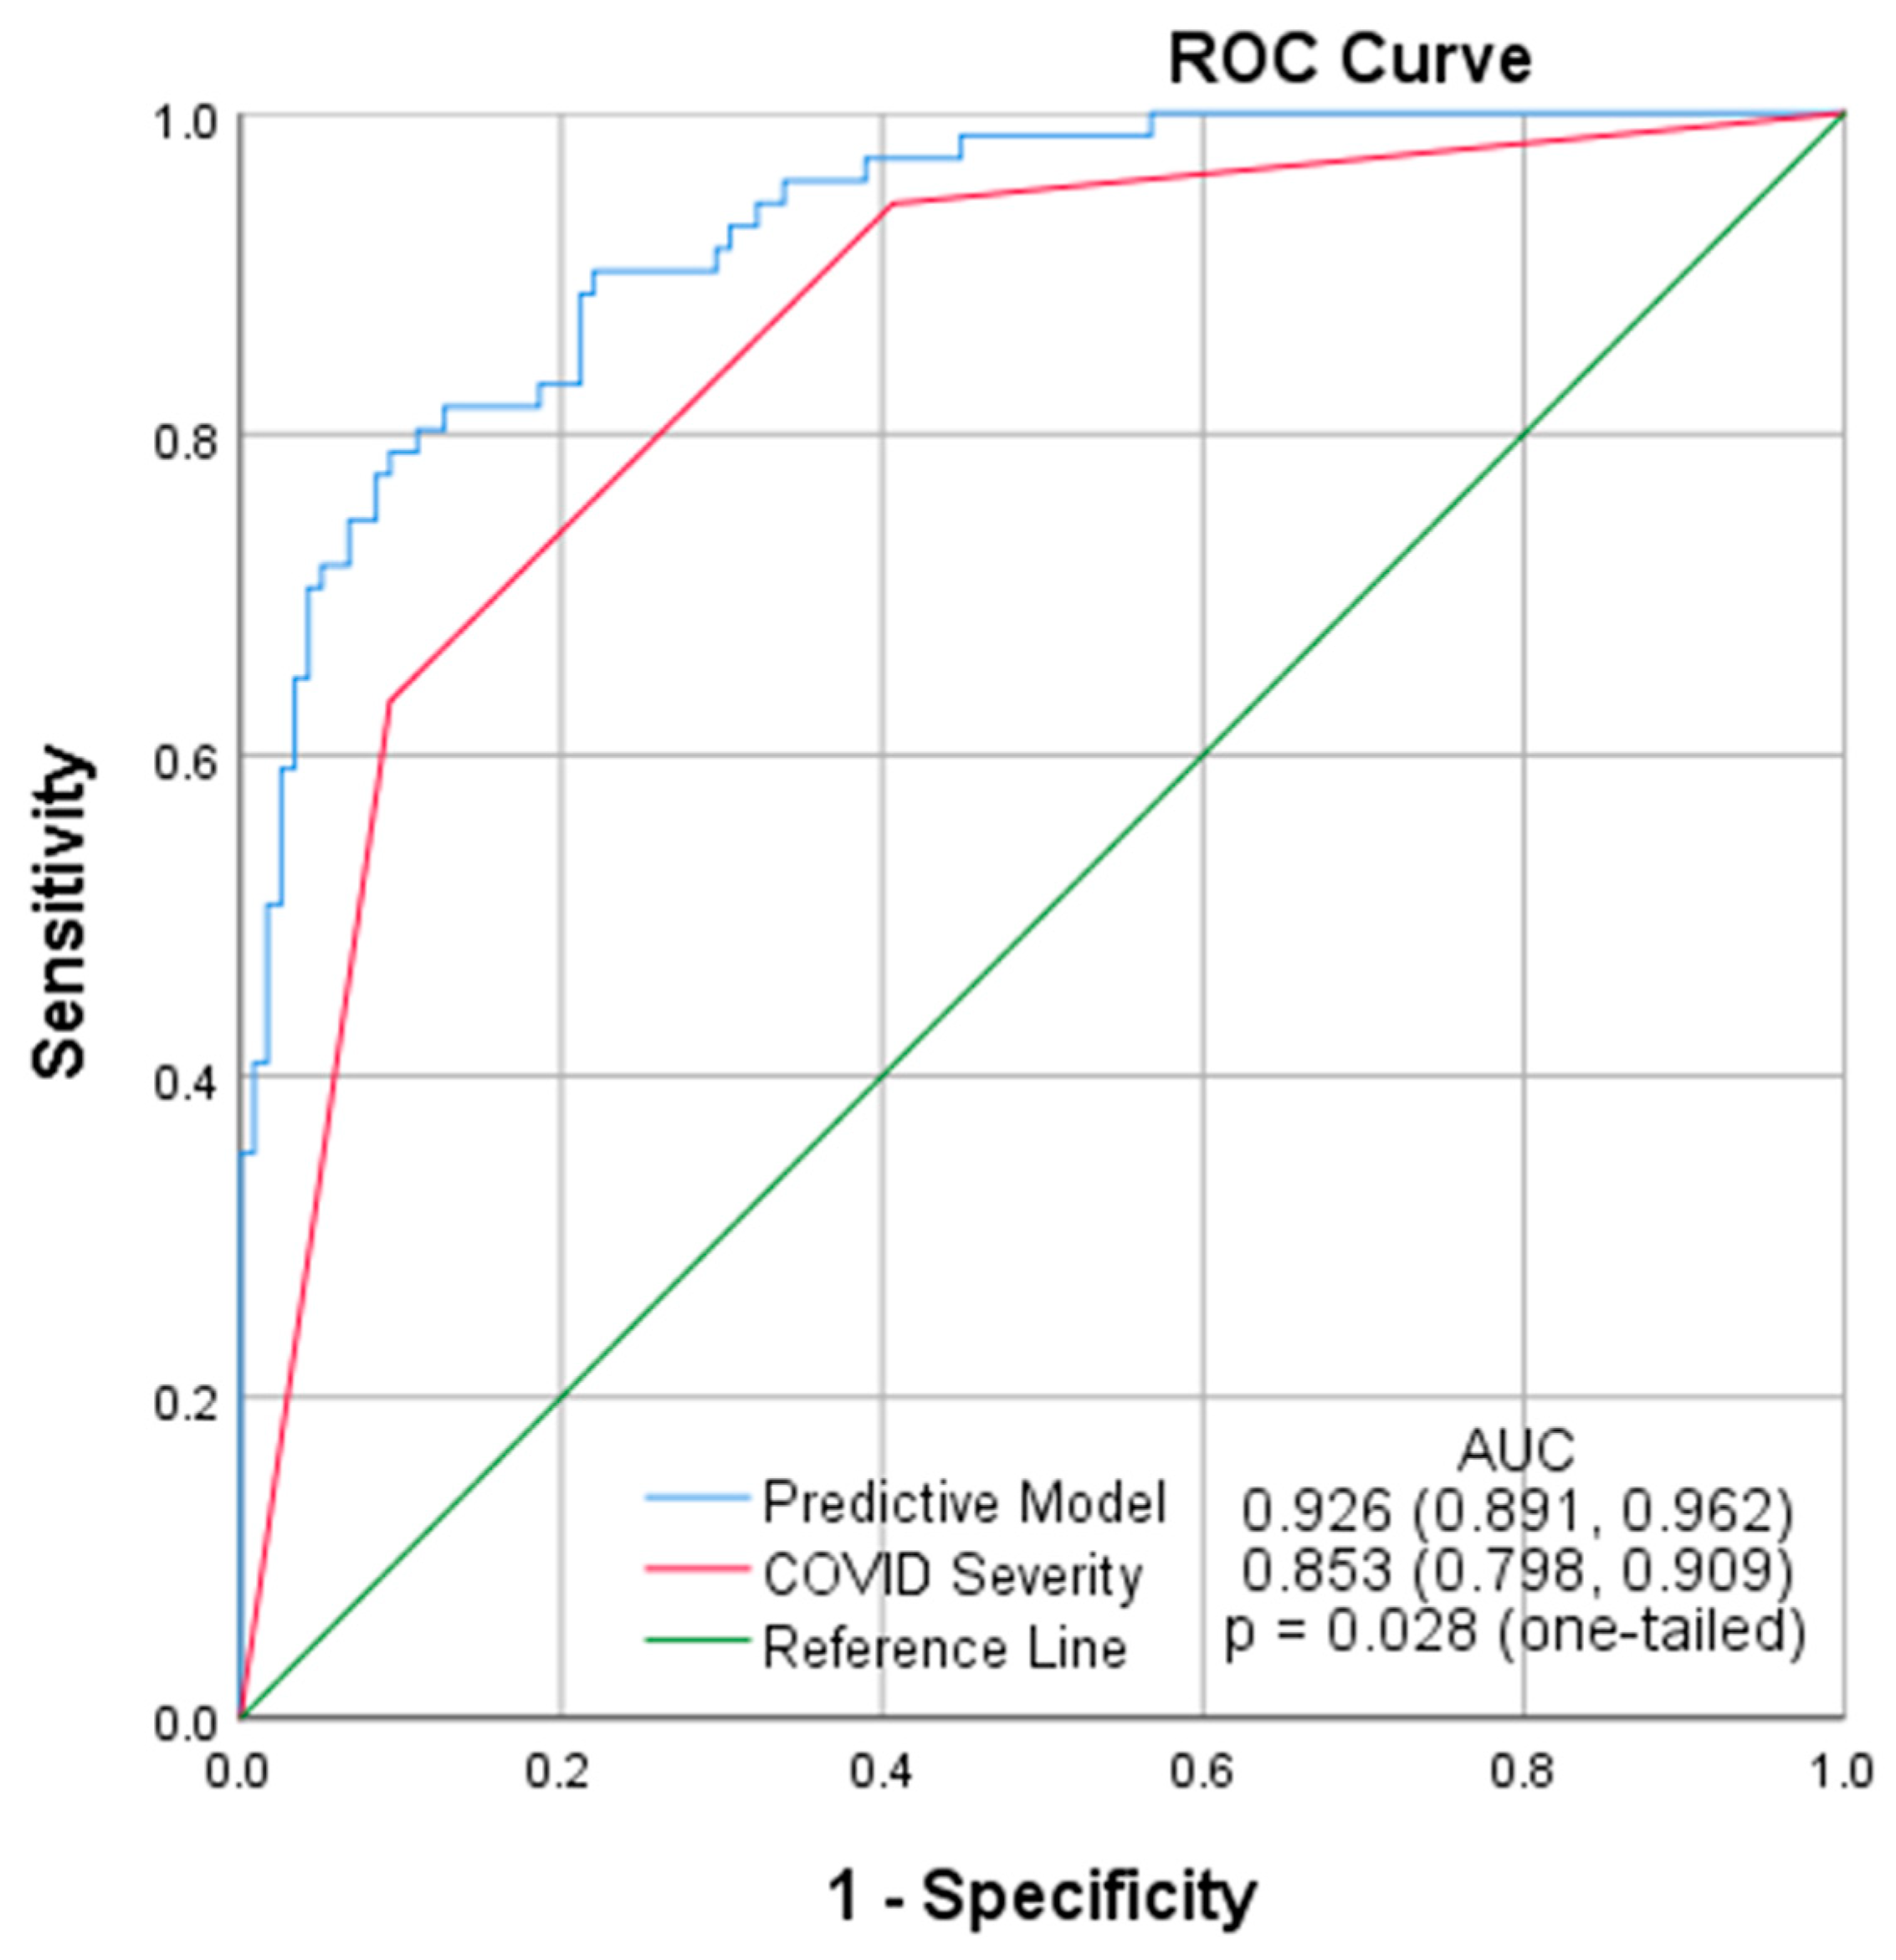

3. Results

4. Discussion